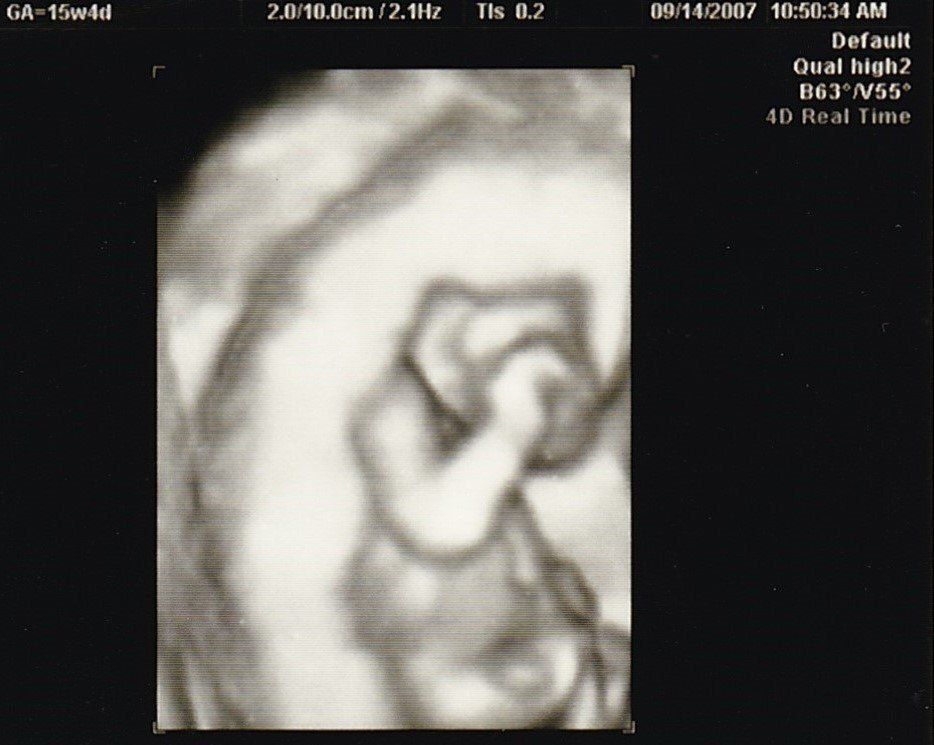

妊娠15週目のエコー写真

やっと安定期に入りました。「性別は、次回の検診のときに聞きたければ教えますよ」と言われていて、今回“男の子”と教えてもらいました。手で目をこすっているような様子など、かわいいな、早く会いたいな、名前どうしようかな、と思いを巡らせていました。退職したため、夫の休みに出産前最後の旅行もしました。